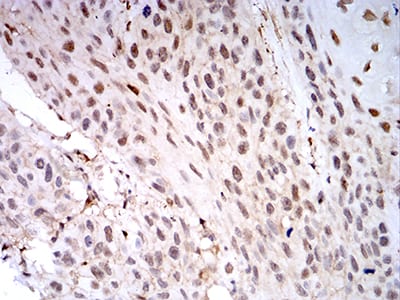

分类: 科研抗体货号: 31032别名: TTF-1; TTF-I应用: IHC,IF,FCM反应种属: Human